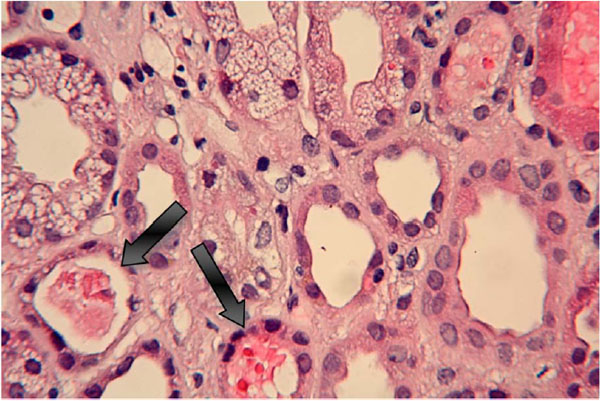

Fig. (5) Lung biopsy shows a necrotizing vasculitis that is associated with hemorrhagic infarct in the lung parenchyma seen with light microscopy with magnification at 10x with a hematoxylin and eosin stain.